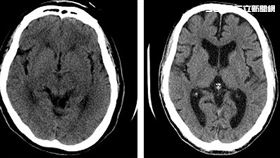

腦血管瘤致命!爆裂1/3恐當場身亡

王亭又因腦血管瘤爆裂死亡,演藝圈內罹患的人不少,包括...